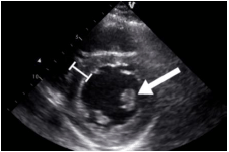

Observe a imagem:

O músculo papilar identificado na seta é o